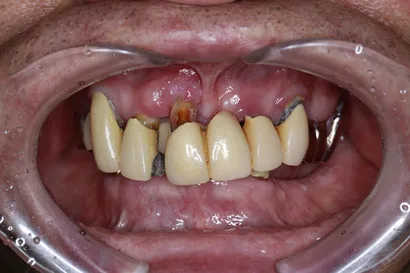

重度虫歯からの全顎インプラント治療

70代 男性

執刀医 Dr.大杉 治療内容 虫歯・歯周病が原因で噛み合わせが崩壊していたので、全顎的なインプラント治療を行い、口腔機能の回復を行いました。

上顎:ピンクポーセレンを用いたフルジルコニアインプラントブリッジ

下顎:奥歯=ジルコニアインプラントブリッジ、前歯=ジルコニアクラウン治療期間 1年6ヶ月 費用 上顎:420万 税抜

下顎:330万 税抜リスク セラミックのすり減りを防ぐために、ナイトガードを作成しています。毎晩使用することで、セラミックを長持ちさせることができます。 -